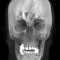

L’Unità Operativa di Radiologia Odontoiatrica, ubicata presso il Dipartimento, è dotata di apparecchiature all’avanguardia nella diagnostica odontostomatologica e del massiccio-facciale. In particolare è presente un’apparecchiatura TC Cone Beam di ultima generazione che consente l’acquisizione volumetrica ad alta definizione ed a bassissima dose dell’intero volume cranio-facciale comprese le articolazioni temporo- mandibolari e le prime vertebre cervicali. Tale esame oggi trova larga applicazione nel campo della diagnostica odontoiatrica e del massiccio facciale, come lo studio pre e post-implantare, la valutazione di elementi dentali inclusi, lo studio di lesioni odontogene e non odontogene, la traumatologia cranio-facciale ed anche la valutazione dei seni paranasali, dell’orecchio e delle articolazioni temporo-mandibolari. Grazie all’acquisizione volumetrica ed alla bassa dose di radiazioni tale metodica è oggi indicata anche nella pianificazione del trattamento ortodontico. Nell’Unità Operativa è inoltre presente l’Orthophos Plus della Sirona Dental System che consente di effettuare esami radiografici standard digitali delle arcate dentarie, dei seni paranasali e delle articolazioni temporomandibolari ed inoltre teleradiografie nelle proiezioni latero-laterale ed antero-posteriore per studio ortodontico. L’Unità Operativa è collegata in rete con i vari reparti della clinica per una rapida consultazione degli esami radiologici.

- TC MASSICCIO FACCIALE